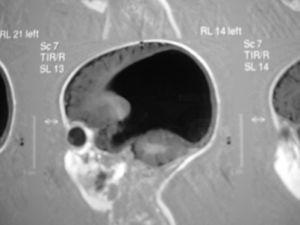

Con la sospecha de miopatía, se realiza estudio necrópsico de biopsias de psoas, cuádriceps, musculatura intercostal y diafragma. Las dos primeras muestran sustitución adiposa sin fibras musculares. Las biopsias de musculatura intercostal presentan intensa infiltración adiposa y fascículos de fibras musculares atróficas alternando con otras normales o hipertróficas y bandas de tejido fibroso entre fascículos. El estudio ultraestructural demuestra intensa infiltración grasa, fibrosis y fibras musculares muy hipotróficas alternando con ocasionales elementos hipertróficos. Las muestras de diafragma están constituidas por fibras musculares relativamente preservadas sin signos de atrofia. El conjunto de hallazgos sugiere una atrofia muscular avanzada concordante con atrofia muscular espinal o enfermedad de Werdnig-Hoffman (AME) (fig. 2). Se realiza estudio genético de portadores de AME en los progenitores del niño mediante análisis cuantitativo mostrando ambos una dosis única del exón 7 del gen SMN1 por lo que la probabilidad de que sean portadores de la deleción del citado gen es superior al 95 % y por ello altamente probable de que el lactante fuese homozigoto para dicha mutación.

Figura 2. Biopsia muscular.